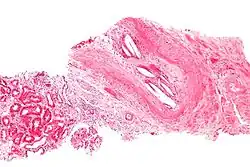

Micrograph of a cholesterol embolus showing the characteristic cholesterol clefts (biconvex white spaces) and a giant cell reaction. Kidney biopsy. H&E stain.

The microscopic examination of tissue (histology) gives the definitive diagnosis. The diagnostic histopathologic finding is intravascular cholesterol crystals, which are seen as cholesterol clefts in routinely processed tissue (embedded in paraffin wax).[7] The cholesterol crystals may be associated with macrophages, including giant cells, and eosinophils.

The sensitivity of small core biopsies is modest, due to sampling error, as the process is often patchy. Affected organs show the characteristic histologic changes in 50-75% of the clinically diagnosed cases.[3][5] Non-specific tissue findings suggestive of a cholesterol embolization include ischemic changes, necrosis and unstable-appearing complex atherosclerotic plaques (that are cholesterol-laden and have a thin fibrous cap). While biopsy findings may not be diagnostic, they have significant value, as they help exclude alternate diagnoses, e.g. vasculitis, that often cannot be made confidently based on clinical criteria.